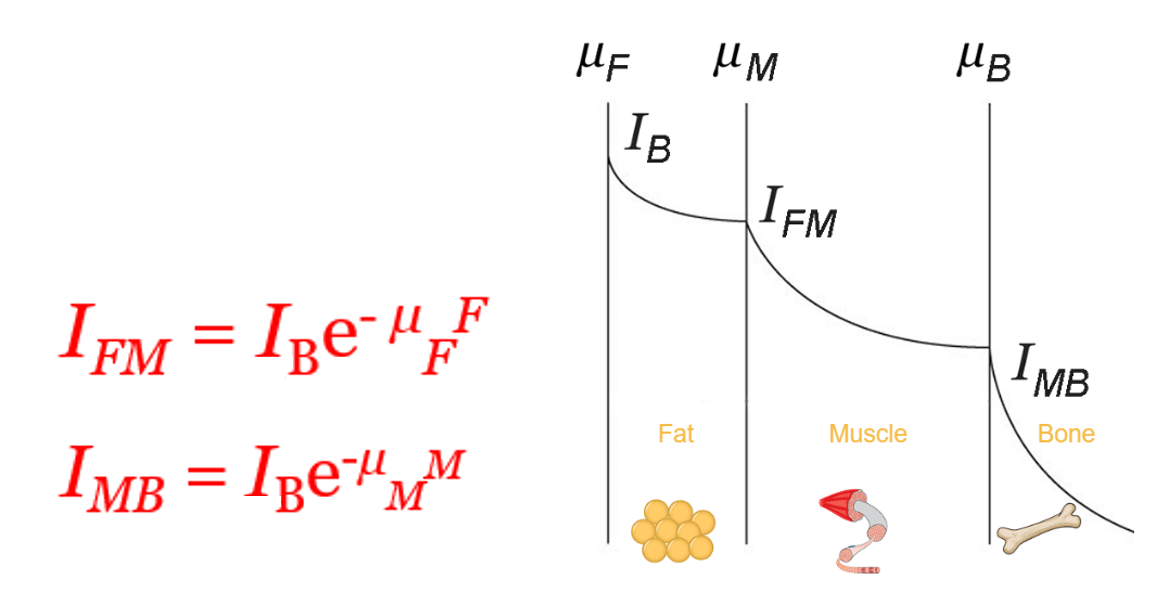

Global Attenuation

The amplitude and intensity of ultrasound waves decrease as they travel through tissues. Theoretically, the attenuation coefficient (μ) in soft tissues, is almost proportional to the ultrasound frequency and depth, with a range between 0.5 and 1 dB / (MHz.cm).

The sound energy is attenuated or weakened as it passes through the tissues. In fact, as the ultrasound wave travels through a medium, parts of it are reflected, scattered, absorbed or refracted.

Absorption

As discussed previously, the absorption is the reduction in the intensity of the sound waves as it passes through a tissue. Most of the energy loss is in the form of heat. The absorption of the sound energy in tissues largely contributes to its overall attenuation, where the degree of attenuation depends on the biological tissue, and the frequency of the wave. The degree of soft tissue attenuation follows an almost linear relationship with the frequency.

- The higher the frequency, the greater the attenuation

- As the attenuation increases, the depth of exploration decreases

The ultrasonic energy is attenuated exponentially while the wave passes through the tissues. We can conclude that the ultrasound wave is strongly attenuated by the bones than other organs.